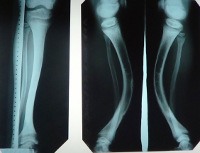

Рентгенологически при фосфат-диабете определяются классические признаки рахита - деформации костей голеней, коленных и тазобедренных суставов, наличие остеопороза (в некоторых случаях может возникать локальный остеосклероз) и остеомаляций. Изменена структура костей - кортикальный слой утолщается, трабекулярный рисунок становится более грубым, диафизы расширены. Нередко костный рентгенологический возраст при фосфат-диабете значительно отстает от фактического, что говорит о задержке развития скелета. Современная генетика позволяет диагностировать практически все типы этого заболевания, как правило, используется метод прямого секвенирования ассоциированных с патологией генов. В некоторых случаях указать на генетическую природу фосфат-диабета может изучение наследственного анамнеза больного.